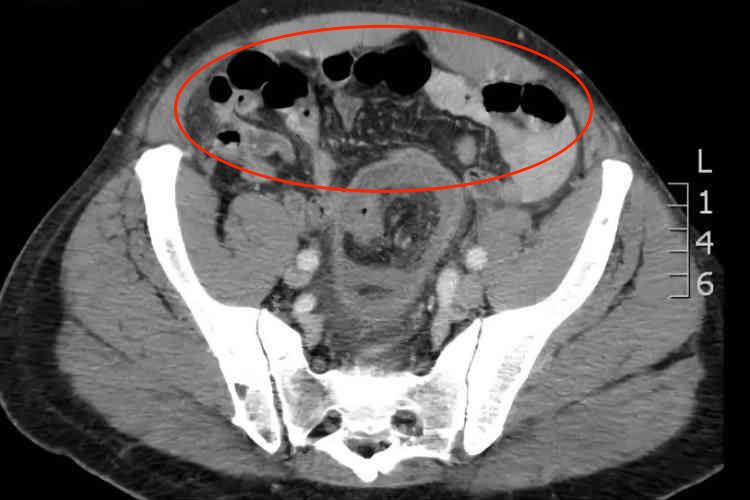

肠梗阻CT影像主要表现为肠管充气扩张,也可见气-液平面、肠壁增厚以及肠管直径增大,同时患者可伴有腹痛、呕吐、腹胀等症状。

CT虽然不是诊断肠梗阻的主要方法,但有时有助于病因的诊断。肠梗阻时CT可显示扩张的肠曲,并可见多个肠腔内气-液平面、肠壁增厚以及直径增大。如果肠管互相融合成团,或与腹壁相连,提示为粘连性肠梗阻。如有肠套叠,则可显示出典型CT征象,出现三层肠壁征。患者还可出现腹痛、呕吐、腹胀等症状。